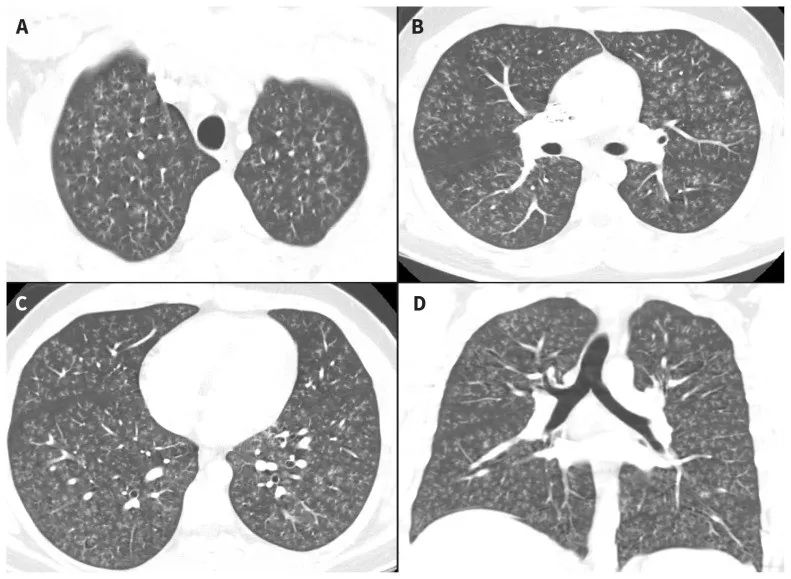

p>晕征是指某些疾病的肺ct 表现 晕征是一种磨玻璃影围绕结节或肿块